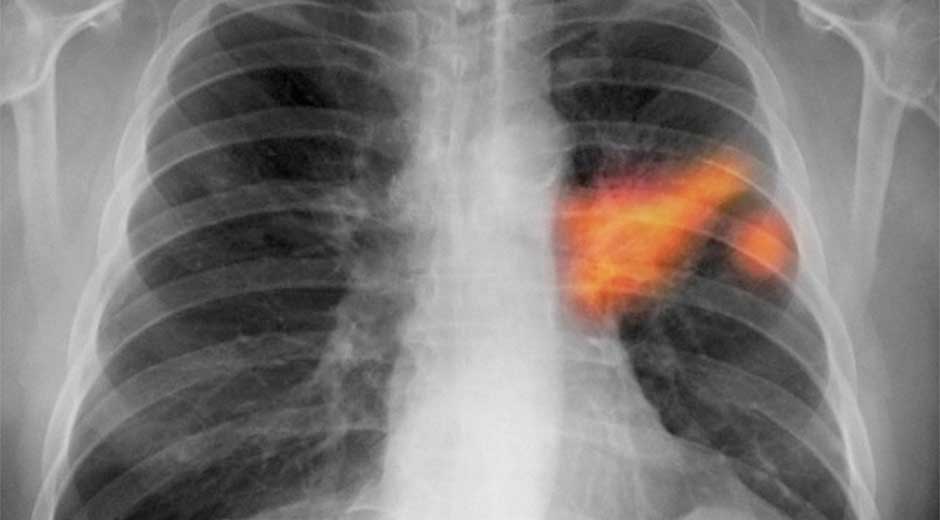

Cáncer de pulmón, el más mortal de todos

[De los tipos de cáncer que existen en el mundo, el de pulmón es el más mortal y en México cobra la vida de 24 personas al día, expuso la presidenta de la asociación civil Respirando con Valor, Mirna Patricia Mondragón.

Comentó que si bien el cáncer de mama y el de próstata son más comunes entre los mexicanos, el de pulmón es el que registra una mayor mortalidad.

“Tenemos más de mil 500 casos cada año y 95 por ciento de ellos va a fallecer casi en el mismo año de su diagnóstico, esto es porque de manera general se detecta en etapas tardías, es decir, en tres o cuatro”, explicó a Notimex.

Por ello, dijo, es necesario que se sensibilice a personal médico para que detecte la enfermedad en etapas más tempranas y hacer entender a la gente los factores de riesgo, pues si bien el principal es el tabaquismo, hay personas que adquieren la enfermedad sin fumar un solo cigarro.

Destacó que la exposición a la contaminación, al asbesto y al humo de leña se han convertido en factores de riesgo muy importantes para la población mexicana.(NOTIMEX)]